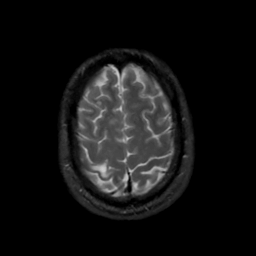

MR Study #6, March 17, 1991 -- Slice #42

[Home][Help][Clinical][Tour 1][Tour 2] Slice 42